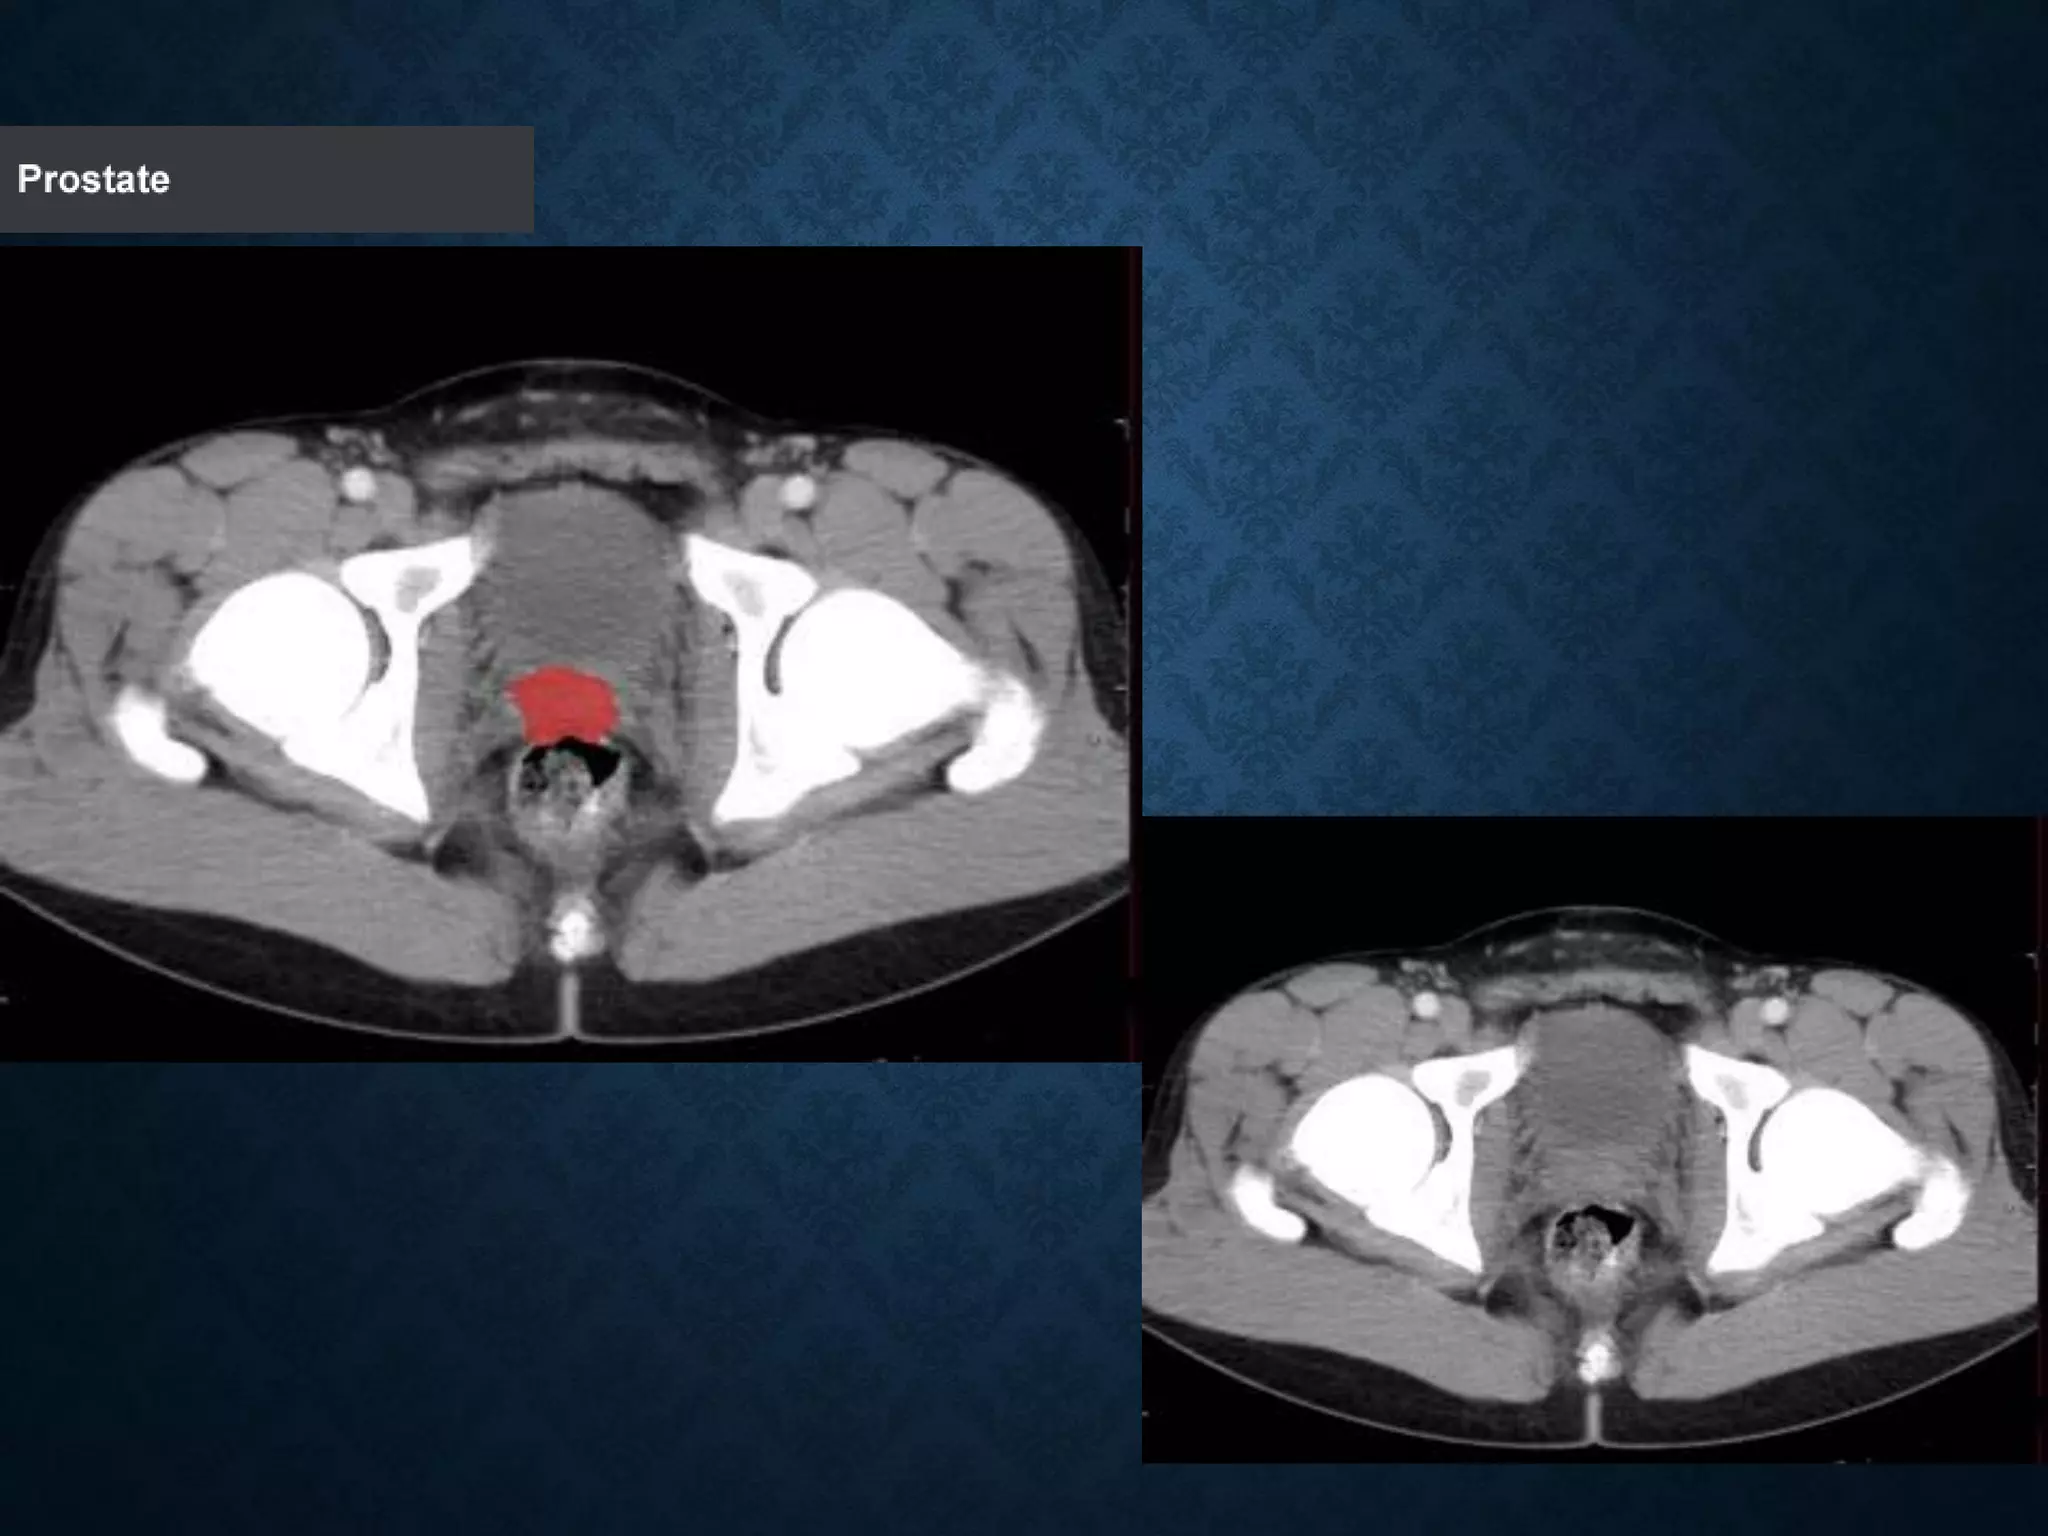

Identify the following structures in the body CT to the right. To view the location of the structure in the image click on

the label at the left and the structure will be indicated in the image. Abdominal CT scans typically begin just above

the diaphragm, so the first slice you see is of the lower chest.